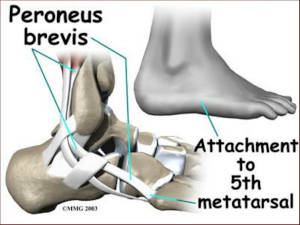

Σπανιότερη είναι η αποφυσιίτιδα της βάσης του 5ου μεταταρσίου λόγω της τάσης του βραχέως περονιαίου μυός (s.Iselin).

Σπανιότερη είναι η αποφυσιίτιδα της βάσης του 5ου μεταταρσίου λόγω της τάσης του βραχέως περονιαίου μυός (s.Iselin).